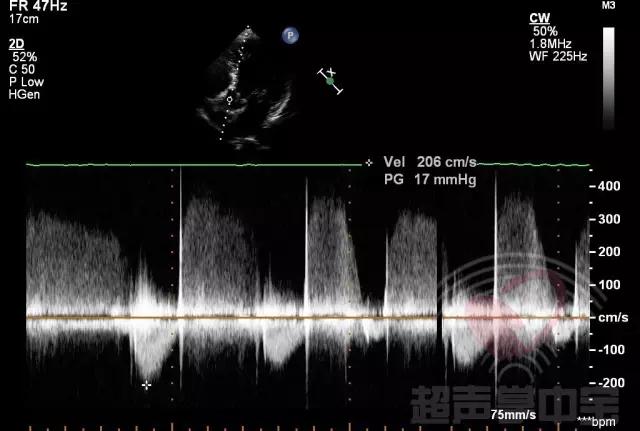

经典病例▏二尖瓣囊肿中竟然全是血液? 图9:CW显示主动脉瓣口流速稍增快,流速2.06m/s,压差17mmHg,并可探及主动脉瓣反流频谱,流速3.9m/s,压差60mmHg。